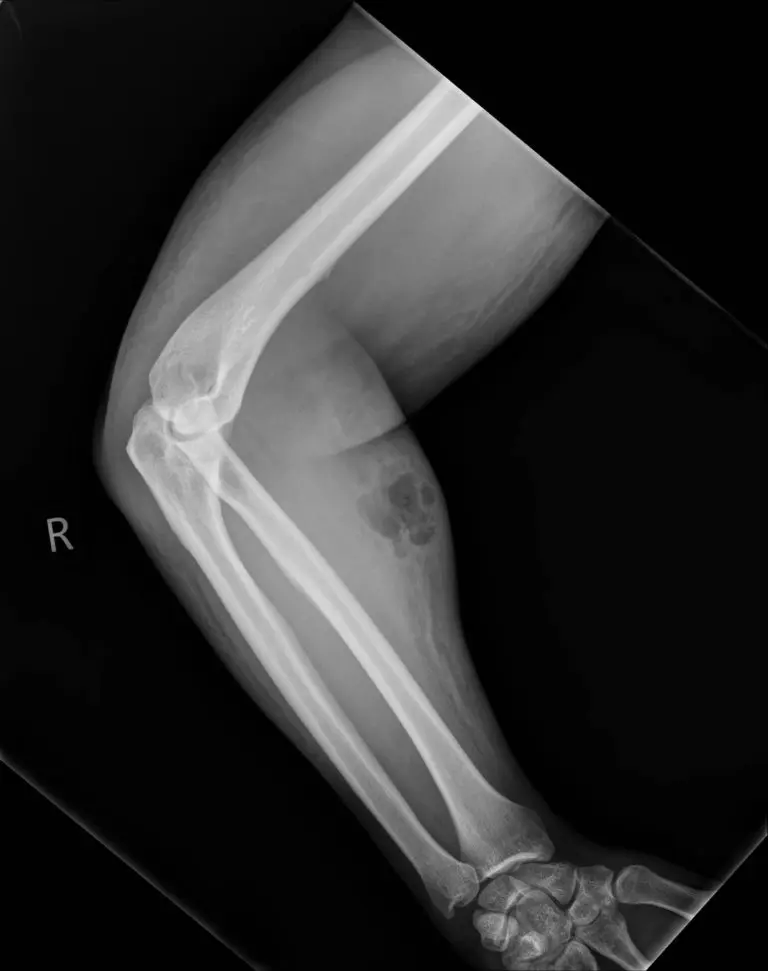

Un Irlandais de 33 ans a expérimenté ce "traitement" pendant 18 mois. Un large abcès sous-cutané s’est étendu sur son bras droit.

Pendant un an et demi, le trentenaire s’était injecté – en intraveineuse et en intramusculaire – sa propre semence tous les mois, grâce à une seringue achetée sur Internet. Un abcès sous-cutané s’est créé et s’est progressivement étendu le long de son bras, et le sperme s’est propagé dans les tissus mous : l'homme souffrait d'une cellulite, une infection bactérienne. Immédiatement, les médecins ont administré à l’homme de 33 ans un traitement antibiotique intraveineux.